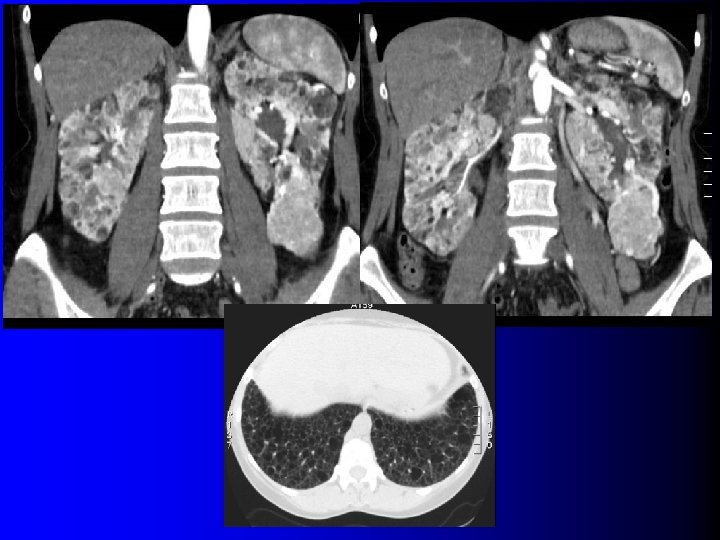

TDM: cas des AML très vasculaires l Très nombreux vaisseaux dysmorphiques – Washout précoce – Diagnostic: l l Contexte (STB, LAM) Micro-anévrysmes visibles en TDM

TDM: cas des AML très vasculaires l Très nombreux vaisseaux dysmorphiques – Washout précoce – Diagnostic: l l Contexte (STB, LAM) Micro-anévrysmes visibles en TDM

Et en cas de STB et/ou LAM? l 13 -33% des AML associés à la STB et/ou à la LAM n'ont pas de graisse en TDM (1, 2) l Impensable de les biopsier tous : diagnostic de probabilité fait sur le contexte l Critère de biopsie ? – Croissance > 0. 5 cm/an (3) (1) Avila NA et al, Radiology 2000; 216: 147 (2) Lane BR et al, J Urol 2008; 180: 836 (3) Patel U et al, Clin Radiol 2005; 60: 665

Et en cas de STB et/ou LAM? l 13 -33% des AML associés à la STB et/ou à la LAM n'ont pas de graisse en TDM (1, 2) l Impensable de les biopsier tous : diagnostic de probabilité fait sur le contexte l Critère de biopsie ? – Croissance > 0. 5 cm/an (3) (1) Avila NA et al, Radiology 2000; 216: 147 (2) Lane BR et al, J Urol 2008; 180: 836 (3) Patel U et al, Clin Radiol 2005; 60: 665

Tumeurs malignes à contenu graisseux l OUI… presque l Quelques rares exceptions dans la littérature – Incorporation de graisse péri-rénale ou sinusale dans une volumineuse tumeur – Métaplasie osseuse avec éléments graisseux de moelle osseuse – Nécrose cholestérolique intra-tumorale (1) Hélénon O et al, Radiographics 1997; 17: 129 (2) Henderson RJ et al, J Urol 1997; 157: 1347 (3) Roy C et al, Br J Urol 1998; 71: 977 (4) Schuster TG et al, AJR 2004; 183: 1402

Tumeurs malignes à contenu graisseux l OUI… presque l Quelques rares exceptions dans la littérature – Incorporation de graisse péri-rénale ou sinusale dans une volumineuse tumeur – Métaplasie osseuse avec éléments graisseux de moelle osseuse – Nécrose cholestérolique intra-tumorale (1) Hélénon O et al, Radiographics 1997; 17: 129 (2) Henderson RJ et al, J Urol 1997; 157: 1347 (3) Roy C et al, Br J Urol 1998; 71: 977 (4) Schuster TG et al, AJR 2004; 183: 1402

Tumeurs malignes à contenu graisseux l Eléments diagnostiques: – Calcifications +++ – Large nécrose intra-tumorale avec petits foyers graisseux – Association avec ADP et thrombus tumoral non graisseux l D'une manière générale, se méfier d'un "AML" à croissance rapide…

Tumeurs malignes à contenu graisseux l Eléments diagnostiques: – Calcifications +++ – Large nécrose intra-tumorale avec petits foyers graisseux – Association avec ADP et thrombus tumoral non graisseux l D'une manière générale, se méfier d'un "AML" à croissance rapide…